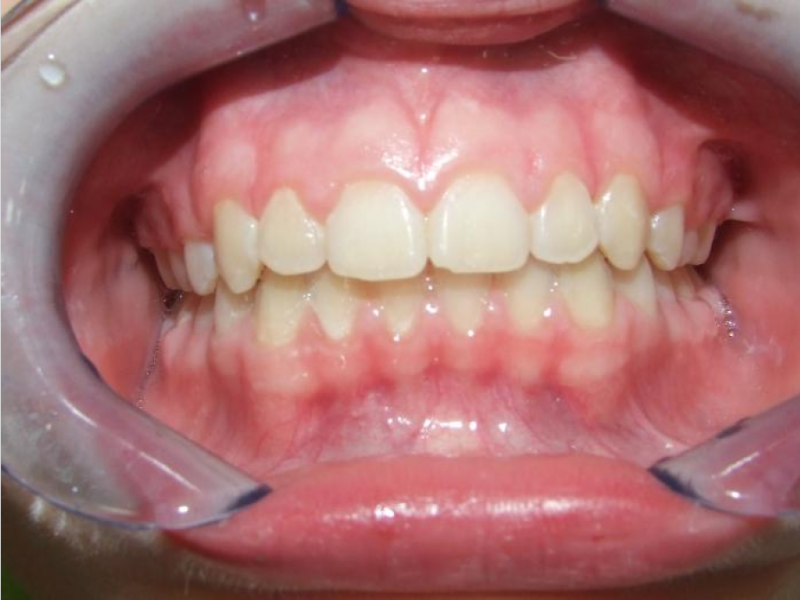

Behandeling Raoul

Duur

van 13-3-14 tot 16-9-15

Beschrijving

Leeftijd bij aanvang: 10 jaar

Bonded Hyrax + volledig vast onderkaak

Volledig vast bovenkaak + expander

Wrap + c-c bar onderkaak

Leeftijd bij afname: 12 jaar

Voor behandeling

Na behandeling